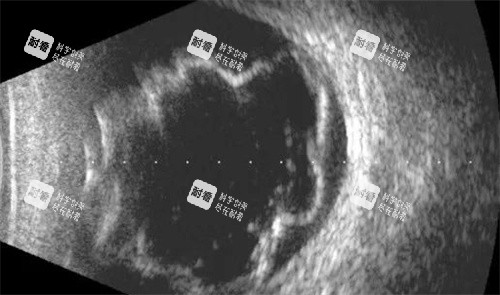

技术特点:擅长复杂视网膜脱离、黄斑病变、糖尿病视网膜病变这些棘手的眼底病,尤其精通小切口手术治疗复杂眼底疾病,手法精细得很。

技术特点:专攻眼底病的诊断和治疗,尤其是视网膜脱离、糖尿病视网膜病变和玻璃体出血的手术治疗,手术成功概率很高。

技术特点:精通各种复杂的视网膜脱离、眼外伤及糖尿病视网膜病变的诊断、治疗和手术,处理过好多疑难杂症。

技术特点:精通眼底病的诊断和治疗,尤其是眼底病的激光光凝术、眼前节激光治疗,用激光治疗眼底病,创伤小,修复快。

技术特点:擅长眼底病的诊断和治疗,尤其是黄斑病变、视网膜脱离的手术治疗,年轻有为,接受新事物快,能运用更新的技术治疗眼底病。